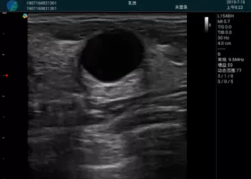

甲狀腺囊性結節(jié),囊壁鈣化,透聲好

甲狀腺囊性占位